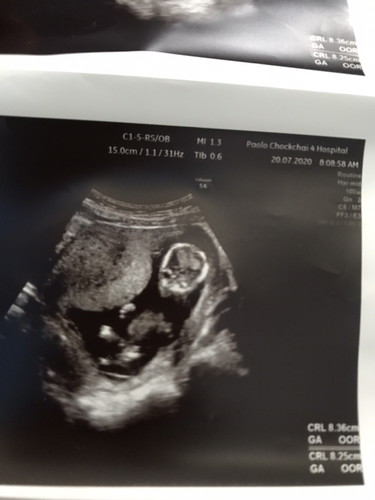

นี้กี่wแล้วค่ะพอดีท้องแรกดูไม่เป็นเลยตอนที่หมอบอกก็ยังงงๆอยู่

อยากทราบว่ากี่w

น่าจะเกือบๆ 4 เดือนแล้วค่ะ